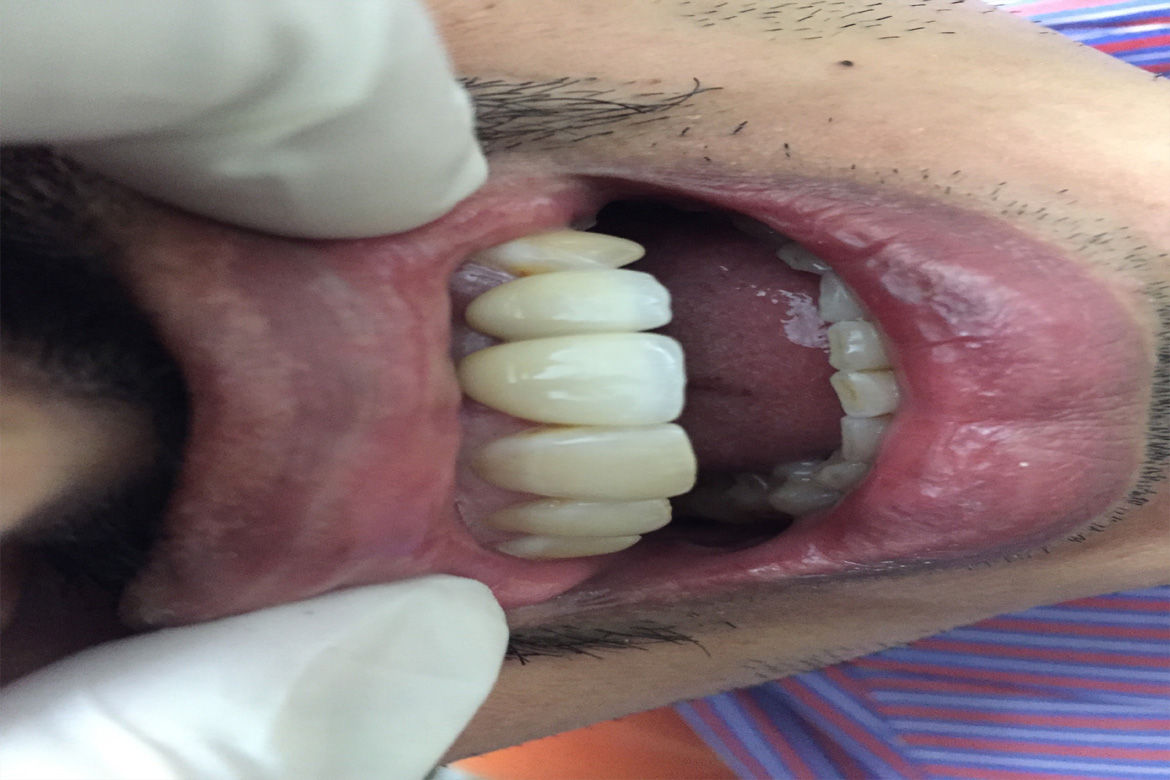

They mimic the natural teeth in form and function.

Although there are several forms of teeth replacement Implants are considered the best as they are durable and functionally potent.